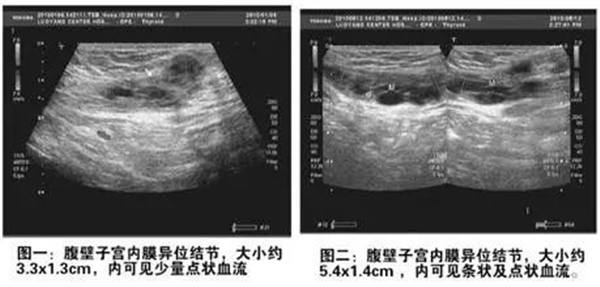

聲像圖特點:1、子宮增大邊界不規則。2、肌瘤結節呈低回聲、等回聲或強回聲。等回聲周邊可有低回聲暈呈假包膜。3、子宮內膜移位或變形。4、膀胱變形,易引起尿貯留。5、肌瘤結節周圍呈環狀及半環狀血流。阻力指數0.6±0.1。

聲像圖特征:1、子宮均勻性增大,邊界規則。2、子宮內膜線前移。3、子宮內回聲不均勻,低回聲、強回聲區,無包膜。4、子宮大小、內部回聲月經前后常有變化。5、腫塊周圍無環狀或半環狀血流,阻力指數約0.6。